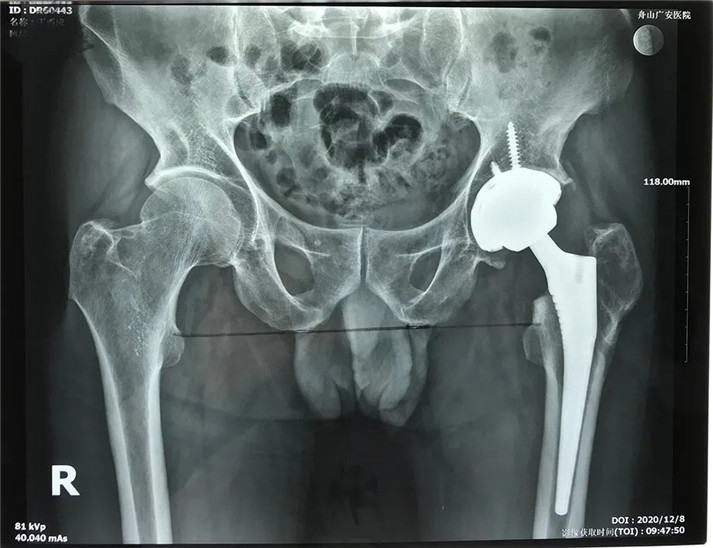

經(jīng)過周密的術(shù)前準(zhǔn)備,在身體符合手術(shù)指征后,丁大哥接受了全髖關(guān)節(jié)置換術(shù)。術(shù)中發(fā)現(xiàn)術(shù)前規(guī)劃產(chǎn)生的假體大小、位置、角度均非常理想,大大縮短了手術(shù)時(shí)間,全程十分順利。術(shù)后,丁先生恢復(fù)良好,次日即可下床活動(dòng)。目前術(shù)后一個(gè)月,可以干活了。對(duì)于此次手術(shù),丁大哥及其家屬表示非常滿意。

術(shù)后